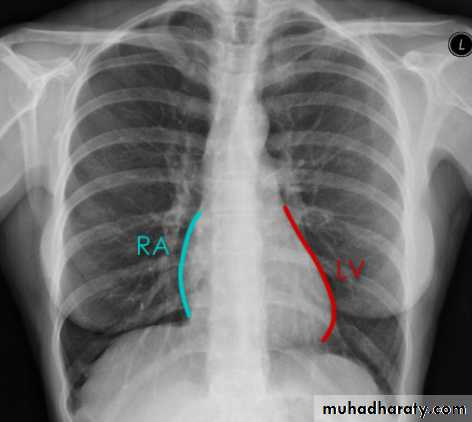

Cardiac borders in AP view